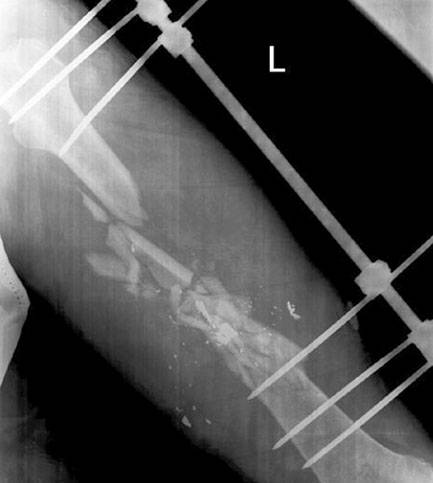

Впоследствии хирурги используют отломки в качестве «трансплантата» и стараются заполнить ими максимум не хватающих дефектов в месте перелома. Для временной фиксации частей кости используется метод скелетного вытяжения, например, чрескостный компрессионно-дистракционный аппарат Илизарова. Принцип действия прост – что не получилось прирастить, выращивается заново. Главное, чтобы было из чего выращивать...

Каким бы эффективным изобретение Гавриила Абрамовича ни было с точки зрения репаративной регенерации, у него есть очевидные сугубо бытовые неудобства. Конечно, в большом количестве случаев человек не теряет мобильность полностью, но носить такую штуку при множественном или сочетанном повреждении придётся примерно от 120 дней, а кроме того – человек привязан к стационару. В случае использования «пластин», «шарниров» и классических гипсовых повязок всё немного проще, разумеется, если не будет осложнений.